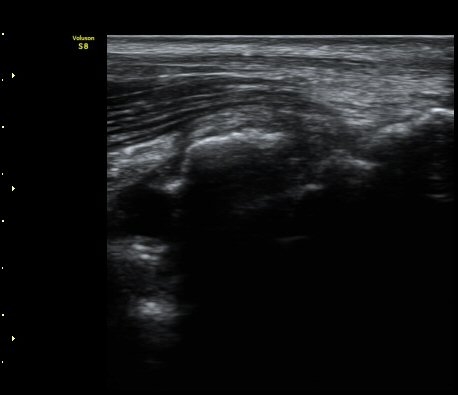

[ÆÈ²ÞÄ¡] ÆÈ²ÞÄ¡ °üÀý³» À¯¸®Ã¼¿¡ ÀÇÇÑ ÆÈ²ÞÄ¡ ÅðÇ༺ °üÀý¿°

¼ºº° / ³ªÀÌ

³²ÀÚ/ 44¼¼

ÁÖÁõ»ó

ÆÈ±ÀÄ¡ ÅëÁõ

ÃÊÀ½ÆÄ °Ë»ç